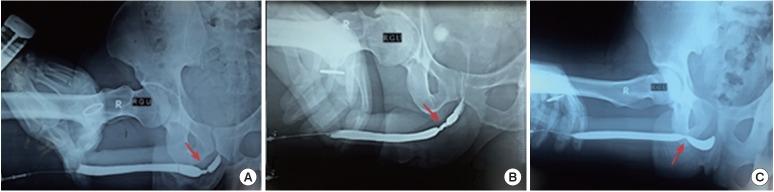

A total of 49 foreign bodies were retrieved from patients' urinary bladders during the study period. The patients ranged in age from 11 to 68 years. Thirty-three patients presented with complaints of haematuria (67.3%), 29 complained of frequency of urination and dysuria (59.1%), and 5 patients reported pelvic pain (10.2%). The circumstances of insertion were iatrogenic in 20 cases (40.8%), self-insertion in 17 cases (34.6%), sexual abuse in 4 cases (8.1%), migration from another organ in 4 cases (8.1%), and assault in 4 cases (8.1%). Of the foreign bodies, 33 (67.3%) were retrieved by cystoscopy, while transurethral cystolitholapaxy was required in 10 patients (20.4%), percutaneous suprapubic cystolitholapaxy was performed in 4 patients (8.1%), and holmium laser lithotripsy was performed in 2 patients (4.08%).

在研究期间,共从患者膀胱中取出49个异物。患者年龄在11岁至68岁之间。33例患者出现血尿症状(67.3%),29例患者有尿频和尿痛症状(59.1%),5例患者报告有盆腔疼痛(10.2%)。置入情况为医源性20例(40.8%),自行置入17例(34.6%),性虐待4例(8.1%),从其他器官迁移4例(8.1%),袭击4例(8.1%)。其中33个异物(67.3%)通过膀胱镜取出,10例患者(20.4%)需要行经尿道膀胱结石碎石术,4例患者(8.1%)进行了经皮耻骨上膀胱结石碎石术,2例患者(4.08%)进行了钬激光碎石术。